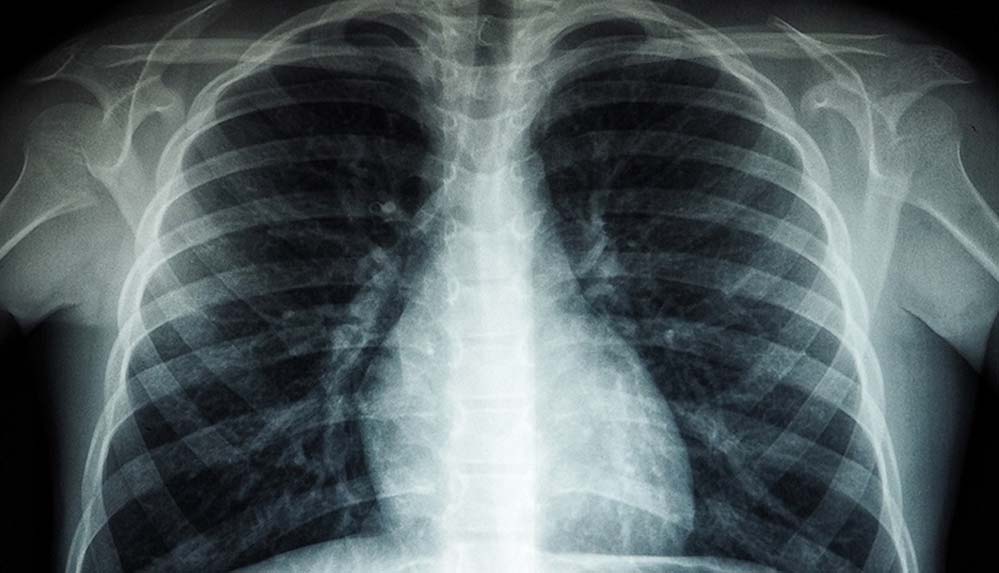

Ghebreyesus, bu hastalığı sonlandırmanın DSÖ’nün öncelikleri arasında bulunduğunu vurgulayarak, “Tüberküloz her yıl 1,5 milyondan fazla kişiyi öldürüyor ve milyonlarca kişiyi daha etkiliyor.” bilgisini paylaştı.

Kovid-19 ile mücadele nedeniyle tüberküloz tedavilerinin aksadığını kaydeden Ghebreyesus, “DSÖ’nün verilerine göre sağlık hizmetlerindeki aksamalardan dolayı yıllık tüberküloz ölümleri son 10 yılda ilk defa artış gösterdi.” ifadelerini kullandı.

Bilim insanı Robert Koch’un verem mikrobunu (Tüberküloz basili) keşfettiği ve hastalığın teşhis ve tedavisinin yolunu açan tarih olan 24 Mart 1882’ye ithafen her yıl 24 Mart, “Dünya Tüberküloz Günü” olarak anılıyor.